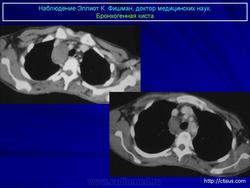

Рентгенологическая картина. При кисте, заполненной жидкостью, обнаруживается округлое или овальное затенение с четкими контурами. Контуры затенения могут изменяться в зависимости от фазы дыхания. При бронхогенной кисте, заполненной воздухом, видна правильной формы полость с чрезвычайно четким контуром, на фоне которой легочный рисунок обычно ослаблен. Более отчетливо просветление прослеживается на томограммах. Небольшой уровень жидкости на дне наблюдается не всегда, однако этот симптом, весьма важен с точки зрения дифференциальной диагностики истинных бронхогенных кист, продуцирующих секрет, от воздушных полостей другого происхождения (булл). Бронхография. Контраст не всегда попадает в полость из-за чрезвычайно узкого сообщения последней с просветом бронхиального дерева.

ID: 22985 Bronchogenic cyst Dr Mostafa Mahmoud El Feki - 10 May 2013 Features consistent of bronchogenic cyst. Differential considerations in...

ID: 10946 Bronchogenic cyst Dr Gagandeep Choudhary - 3 Oct 2010 CT through the chest demonstrates a large fluid density cystic structure...